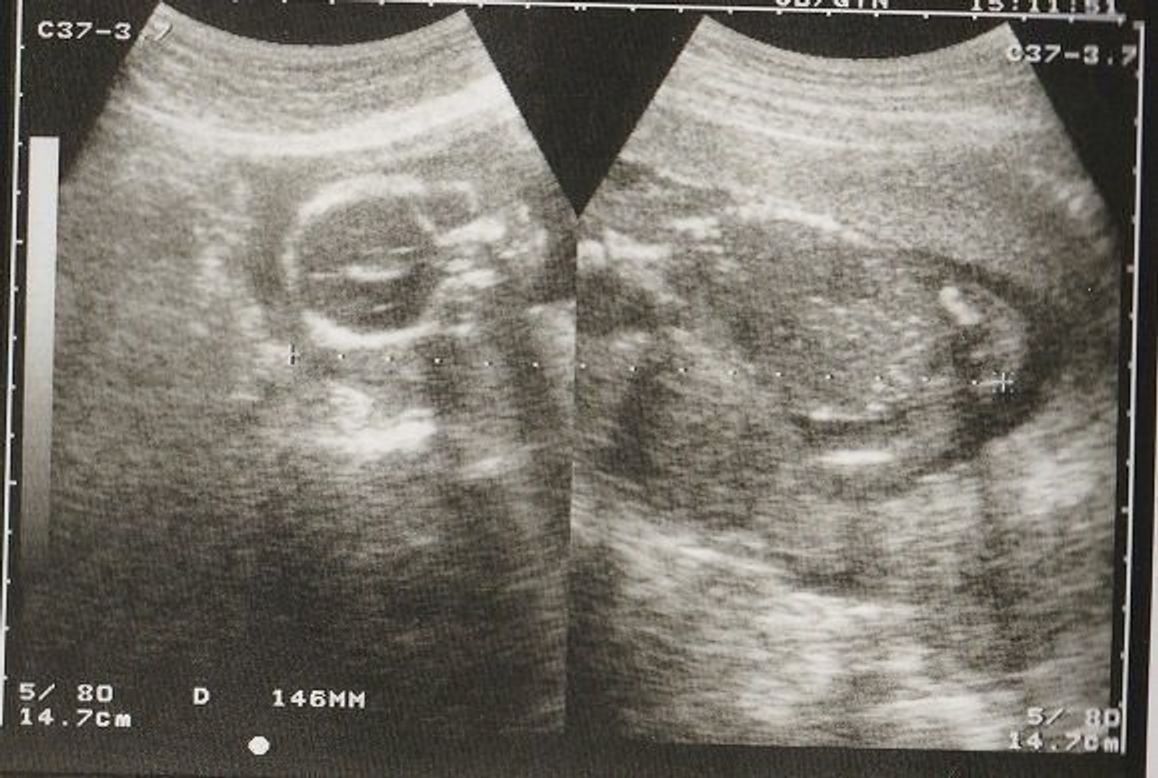

4dエコー撮影 広橋産婦人科クリニック

これは先ほど説明した 胎児の推定体重を、「胎児発育曲線」グラフに当てはめて判断しています。 胎児発育曲線グラフとは、正期産(37週~41週のお産)で生まれた 正常な体重の赤ちゃんの胎児時代の推定体重データを元に、 妊娠週数ごとの基準値、つまり平均値をグラフ化したものです。 妊娠18週は胎動を初めて感じたり、赤ちゃんの性別が判明するなど楽しみがたくさん。 妊娠5か月目にはいり、つわりや妊娠初期症状が落ち着いてきたママも多いですね。 妊娠18週の特徴 子宮の大きさが頭くらい お腹の膨らみが目立ち、ママの体全体が